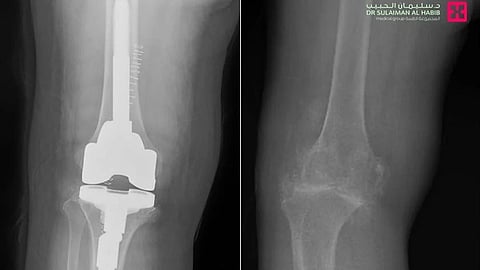

وقال د. حمد الشهراني استشاري جراحة العظام والمفاصل الصناعية، والطب الرياضي، رئيس الفريق الطبي المعالج، أن المراجعة جاءت إلى المستشفى على كرسي متحرك، مشتكية من عدم القدرة على المشي، وآلام حادة وتورم وتشوه في مفصل الركبتين، بالإضافة إلى تيبس وصعوبة في ثني الركبة، وخضعت لفحوصات طبية دقيقة، حيث أكدت صور الأشعة الطبية، وجود خشونة حادة بمفصل الركبة، مع تآكل بالعظم وارتخاء الغضاريف التي تحيط به وتحميه من الاحتكاك بشكل مباشر، وسبب كل ذلك في عدم قدرتها على الحركة وتقوساً بالركبة، وتمت مناقشة الحالة وفق معطيات التشخيص من قبل الفريق الطبي، ووضع خطة علاجية متكاملة، وأجريت لها عملية استبدال مفصل، في تدخل طبي استمر لنحو "90" دقيقة وقد تكللت ولله الحمد بالنجاح، وتم تحويلها مباشرة إلى جناح التنويم، حيث أمضت "4" أيام محاطة بالعناية الطبية الحثيثة، وبدأت في المشي على قدميها بعد العملية بساعات، وواصلت خلال تنويمها العلاج بالأدوية، بالإضافة إلى تنفيذها لبرنامج علاج طبيعي متكامل، وتحسنت حالتها الصحية باضطراد، إلى أن غادرت المستشفى وهي بصحة جيدة، حيث زال التقوس واستعاد الساق شكله الطبيعي، كما أنها تخلصت من الآلام وغيرها من الأعراض الحادة، التي كانت تنغص حياتها، إضافة إلى أنها استعادت قدرتها الكاملة على الحركة، حيث غادرت المستشفى إلى منزلها مشياً على قدميها وبحالة نفسية ممتازة.